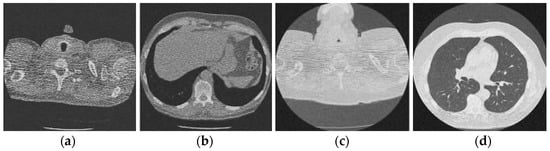

Figure 3 shows the corruption of a CT image after the addition of 20% Gaussian noise. The degradation in image quality is visible to the naked eye without aid when compared to the original CT image. Figure 4, Figure 5, Figure 6, Figure 7, Figure 8, Figure 9, Figure 10 and Figure 11 show the denoised CT images, corresponding to CT images in Figure 3 and generated from various denoising models. The results show a discernible reduction in both the gaussian noise introduced, as well as the noise present in the original CT image whilst safeguarding the finer details present in it.

Figure 3.

Noisy CT image data set after inserting 20% noise); (a) Noisy CT1 image; (b) Noisy CT2 image; (c) Noisy CT3 image; (d) Noisy CT4 image.